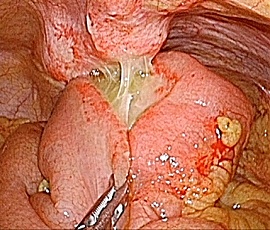

急性腹症にて救急受診。CT検査にて、下腹部正中右側の回腸遠位部に腸管壁肥厚と周囲の脂肪織濃度上昇および微小な遊離ガス像を認め、内部に嚢胞性病変を認めた。精査の結果、メッケル憩室炎、穿孔と診断。緊急手術(腹腔鏡下小腸切除術手術(単孔式))を施行した。

手術画像